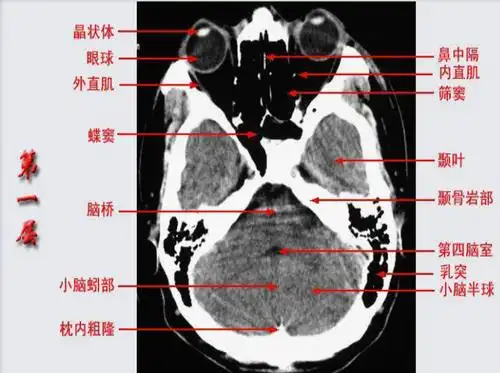

头颅ct断层解剖图片